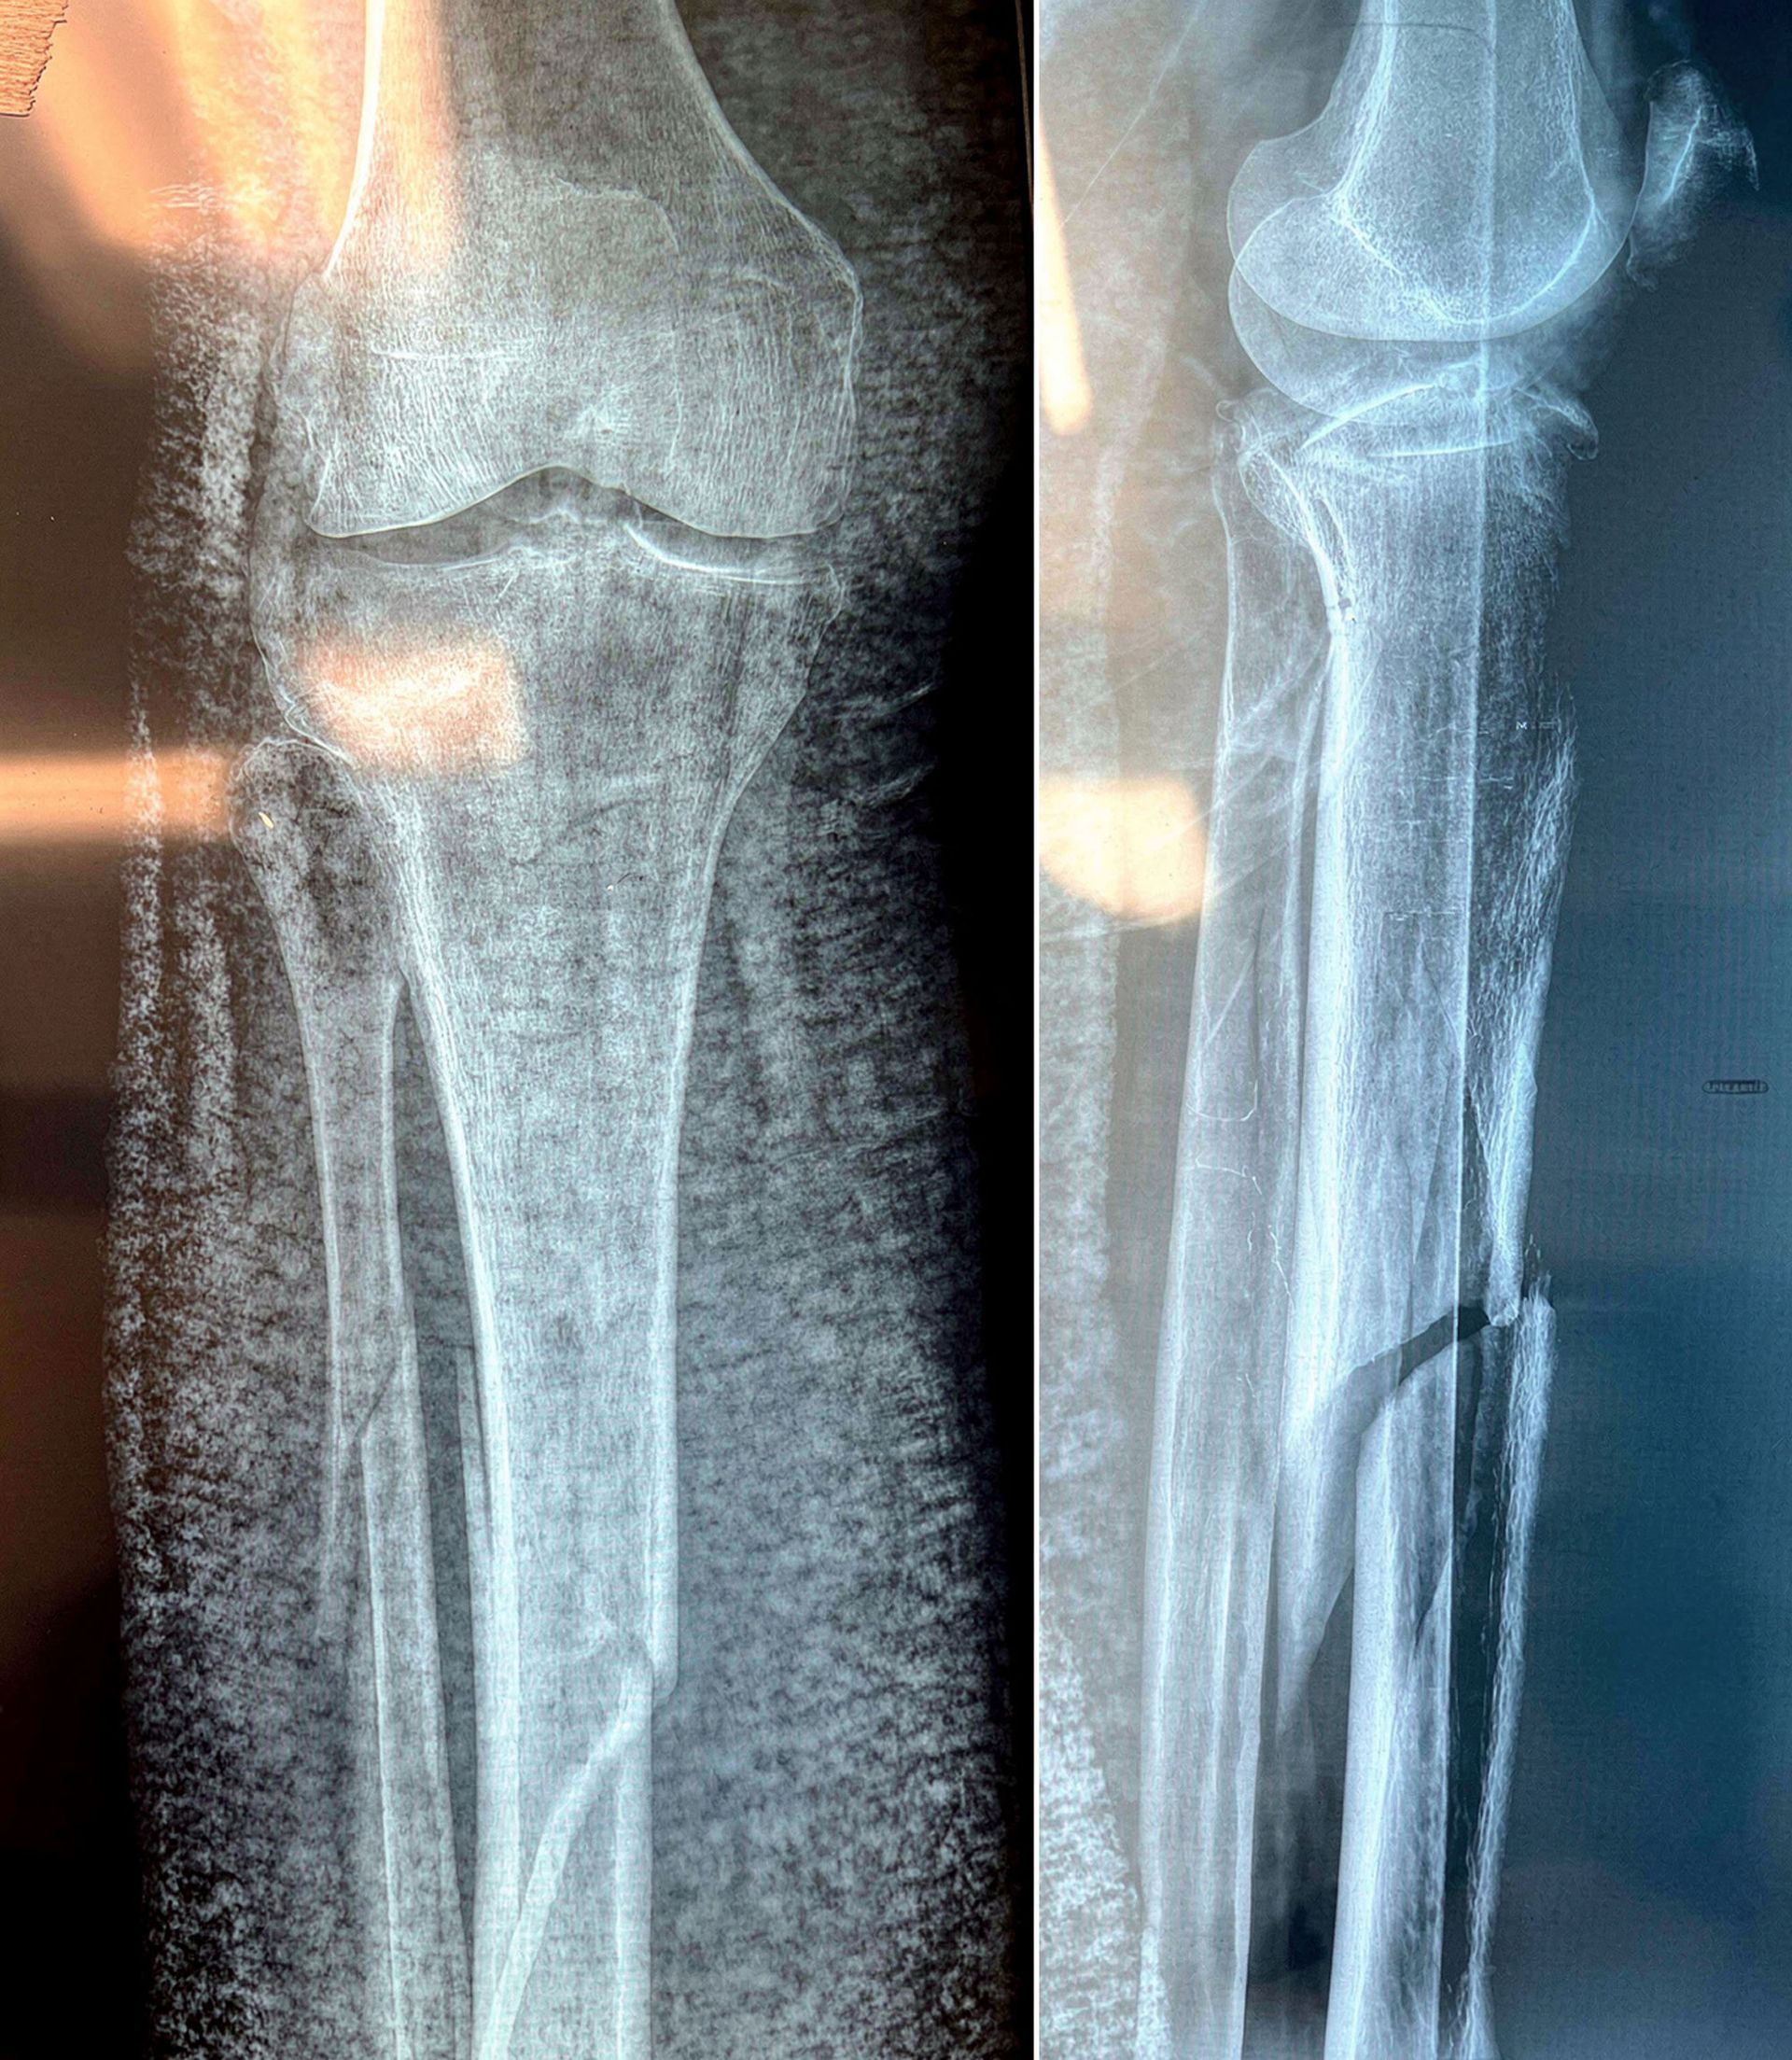

Σοβαρό ενδαρθρικό κάταγμα κνημιαίου πλατώ (Schatzker VI) — υψηλών απαιτήσεων αποκατάσταση με στόχο ανατομική ανάταξη και λειτουργικότητα γόνατος.

Αντιμετωπίσαμε ένα από τα πιο απαιτητικά και σύνθετα τραύματα στην ορθοπαιδική: σοβαρό ενδαρθρικό κάταγμα κνημιαίου πλατώ, Schatzker VI.

Το κάταγμα τύπου VI κατά Schatzker είναι το πιο βαρύ είδος κατάγματος του κνημιαίου plateau. Χαρακτηρίζεται από:

- Διπλοκονδύλιο κάταγμα (έσω + έξω plateau)

- Αποσύνδεση μεταφύσεως–διάφυσης (metaphyseal–diaphyseal dissociation)

- Συχνά συνοδό σοβαρή βλάβη μαλακών μορίων

Κλινική εικόνα

- Έντονος πόνος

- Αδυναμία φόρτισης

- Σημαντικό οίδημα / αιμάρθρο

- Παραμόρφωση

Διάγνωση

Απεικόνιση

- Ακτινογραφίες (AP – lateral)